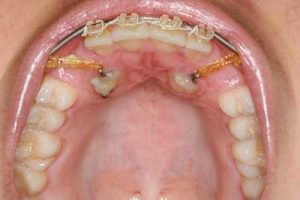

معمولاً ابتدا براکت گذاشته میشود (حداقل برای فک بالا) تا فضای لازم در قوس دندانی ایجاد شود. در صورتی که دندان نیش شیری هنوز نیفتاده است، موقتاً در جای خود حفظ میشود تا زمانی که فضای کافی برای بیرون زدن دندان نیش دائمی آماده باشد. در این زمان جراح دهان دندان نیش نهفته را نمایان میکند و ارتودنتیست با کمک براکت آن را به سمت بیرون میراند.

این عمل جراحی بسیار ساده بوده و در کلینیک دندانپزشکی انجام میشود. در این عمل، بافت لثه روی دندان نهفته باز میشود تا دندان نمایان شود. در صورتی که دندان نیش شیری هنوز وجود نیفتاده باشد، در این زمان کشیده میشود. پس از این که دندان نهفته نمایان شد، براکت ارتودنسی به آن متصل میشود.

به نگین براکت چسبانده شده به دندان نیش نهفته، یک زنجیر مینیاتوری متصل شده است. زنجیر طلایی به سیم ارتودنسی (آرچ وایر) وصل میشود. گاهی اوقات ممکن است دندان نهفته که روی آن باز شده است، به کمک بخیه کردن لثه به سقف دهان و ایجاد پنجره، کاملا نمایان بماند. اما در بیشتر مواقع بافت لثه به جایگاه قبلی خود بازگردانده شده و بخیه میشود و تنها زنجیر چسبانده شده به دندان نیمه نهفته قابل مشاهده باقی میماند و از سوراخ کوچکی در لثه بیرون میزند.

مدت کوتاهی پس از جراحی (یک تا ۱۴ روز) بیمار به ارتودنتیست مراجعه میکند. یک حلقه کشی به زنجیر متصل شده به دندان نیش وصل میشود تا دندان را به سمت خارج از لثه هدایت کند. در اینجاست که فرآیند حرکت دادن دندان به موقعیت مطلوب خود در قوس دندانی آغاز میگردد. این کار باید به دقت تحت کنترل قرار داشته باشد. این فرایند طولانی و تدریجی بوده و ممکن است یک سال طول بکشد. توجه داشته باشید هدف از درمان، بیرون زدن دندان نهفته در جایگاه درست است نه کشیدن آن. به محض که دندان به موقعیت نهایی رسید، بافت لثه اطراف آن برش خورده و بالا زده میشود تا دندانپزشک از سالم و محکم بودن آن و توانایی عملکرد مادام العمر جویدن، اطمینان حاصل نماید. در برخی شرایط به خصوص در مواردی که دندان باید مسافت طولانی را طی کند تا به موقعیت مطلوب برسد، ممکن است جراحی کوچکی در لثه انجام شود تا بر حجم بافت لثه در موقعیت جدید دندان افزوده شود تا از عملکرد نرمال آن اطمینان حاصل شود.